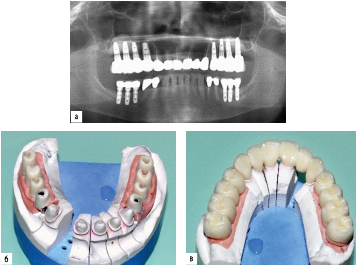

image

Рис. 2.9.5. Несъемный протез на имплантатах на верхней челюсти и съемный на имплантатах на нижней челюсти с замковой фиксацией: а - ортопантомограмма челюстей с имплантатами; б, в - балка на имплантатах и покрывной протез с жесткой замковой фиксацией к балке на нижней челюсти; г - металлокерамический протез на имплантатах на верхней челюсти; д - протезы на имплантатах в полости рта